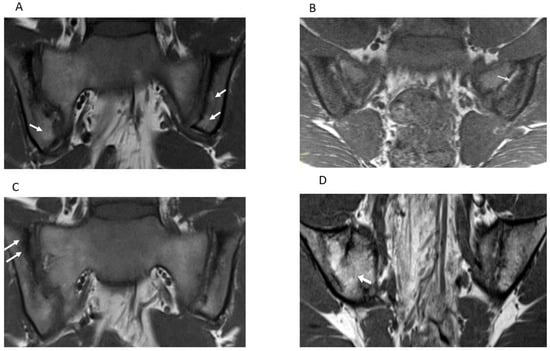

| Features | Definitions | Scores |

|---|---|---|

| Inflammation MRI Components | Score range/slide | |

| BME | An ill-defined area of high bone marrow signal intensity † within the subchondral bone in the ilium or sacrum on fluid-sensitive images | Score 4 quadrant/SIJ 0/1, range 0–8 |

| BME Intensity | Hyperintensity of the marrow edema using the presacral veins as reference | Score each SIJ 0/1, 0–2 |

| BME Depth | Continues to increase the signal of depth ≥ 5 mm/ ≥ 1 cm from the articular surface | Score each SIJ 0/1, 0–2 |

| Capsulitis | High signal on fluid-sensitive and/or post-contrast enhancement involving the SIJ capsule | Score halves / SIJ 0/1, 0–4 |

| JSI | Increased signal on fluid-sensitive or contrast-enhanced T1-weighted images within the joint space of the cartilaginous portion of the SIJ | Score halves/ SIJ 0/1, 0–4 |

| Enthesitis | High signal in bone marrow and/or soft tissue on a fluid-sensitive sequences or a contrast-enhanced T1-weighted sequence at sites where ligaments and tendons attach to a bone | Score each case 0/1, 0–1 |

| Structural MRI Components | ||

| Sclerosis | A substantially wider than normal area of low subarticular bone signal on T1-weighted and fluid-sensitive images (of ≥5 mm in adolescents) | Score 4 quadrants/SIJ 0/1, 0–8 |

| Erosion | Bony defect (or irregularity with associated bone marrow edema, sclerosis, or fatty lesion) at the osteochondral interface involving both contour and signal on both T1-weighted and fluid-sensitive images | Score 4 quadrants/SIJ 0/1, 0–8 |

| Fat Lesion | Increased homogenous signal intensity on T1-weighted non-FS image in subchondral bone with a distinct border | Score 4 quadrants /SIJ 0/1, 0–8 |

| Backfill | A bright signal on a T1-weighted sequence in a typical location for an erosion, with signal intensity greater than normal bone marrow, and meeting the following requirements. 1. It is associated with complete loss of the dark appearance of the subchondral cortex at its expected location. 2. It is clearly demarcated from adjacent bone marrow by an irregular band dark signal reflecting sclerosis at the border of the original erosion | Score halves/SIJ 0/1, 0–4 |

| Ankylosis | Presence of signal equivalent to regional bone marrow continuously bridging a portion of the joint space between the iliac and sacral bones | Score halves/0/1, 0–4 |